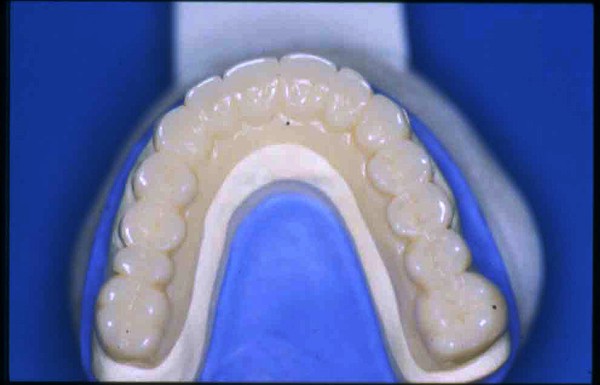

APRECIACIONES DIAGNÓSTICAS EN BASE A LA APERTURA MENTAL DEL CLÍNICO FRENTE A LO QUE EL PACIENTE PROPONE EN MUCHAS OCASIONES , LA DEMANDA DE LOS PACIENTES NOS INCLINAN A FOCALIZAR NUESTRA ATENCIÓN EN LAS PIEZAS DE LAS CUALES EL ENFERMO SE QUEJA. PACIENTE SEXO FEMENINO, 55 AÑOS, SE PRESENTA A LA CONSULTA DERIVADA POR COMPAÑERO GENERALISTA, QUIEN LLEVA MESES PROCEDIENDO A LA «DESINFECCIÓN» DE UN PRIMER PREMOLAR IZQUIERDO, EL QUE SE PRESENTA ABIERTO EN SU CONDUCTO EN EL AFÁN DE PERMITIR EL ESCAPE DE GASES DE UNA GANGRENA PULPAR. A LA INSPECCIÓN CLÍNICA SE OBSERVAN FACETAS PARAFUNCIONALES DE TERCER GRADO , ASINTOMÁTICAS, CON EVIDENTES DIFICULTADES MASTICATORIAS Y ESTÉTICAS , FALTA TOTAL DE SUS MOLARES INFERIORES, Y ADELANTAMIENTO PRONUNCIADO DE SU MANDIBULA, LA QUE CUESTA MANIPULAR DEBIDO A LA SITUACIÓN DE ESPASMO DE CASI TODA SU MUSCULATURA GNATICA. SE ESTUDIA EL CASO RADIOLOGICAMENTE, Y SE RELAJA EL SISTEMA MEDIANTE LAM. DE LONG REALIZANDO UN MONTAJE EN LA ORC OBTENIDA. NO SATISFECHOS CON EL RESULTADO, CONFECCIONAMOS UN JIG DE LUCIA, EL QUE DEJAMOS EN BOCA TODA UNA NOCHE, AL CABO DE LA CUAL REALIZAMOS UN NUEVO REGISTRO REALIZAMOS UN ENCERADO RÁPIDO DEL CASO, Y CONFECCIONAMOS UNA ESTRUCTURA OCLUSAL PLASTICA, QUE ADEMÁS REPONGA EL ASPECTO ESTÉTICO PERDIDO (FÉRULA DE RELAJACIÓN DE COMPONENTE ESTÉTICO), LO QUE PERMITE AL ENFERMO LUEGO DE DOS DÍAS DE USO, NO SOLO CORROBORAR LA COMODIDAD MASTICATORIA Y LA FALTA DE SÍNTOMAS MUSCULARES, SINO TAMBIÉN OBSERVAR APROXIMADAMENTE LA DIFERENCIA ENTRE LA SITUACIÓN INICIAL Y LO QUE PUEDE LOGRARSE MEDIANTE EL TRATAMIENTO. EL PACIENTE ADVIERTE LA MEJORÍA DE LA SITUACIÓN. ACEPTADO POR PARTE DEL MISMO EL TRATAMIENTO SUGERIDO, CREAMOS UN JUEGO COMPLETO DE PROVISORIOS EN BASE AL ENCERADO, Y PROCEDEMOS A TRATAR LA INFRAESTRUCTURA, QUE CONSISTE EN LAS ENDODONCIAS, SUS REFUERZOS A PERNOS DE ORO, LOS ASPECTOS PERIODONTALES DEL CASO, Y DOS IMPLANTES INFERIORES CON TÉCNICA SEMISUMERGIDA ,DE 5 MM DE ANCHO POR 12 DE LONGITUD, CON ANILLO DE ZIRCONIO , A LA ESPERA DE OSTEOINTEGRACIÓN, TRANSCURREN TRES MESES EN EL USO DE UNA NUEVA OCLUSIÓN CONSTITUIDA POR LOS PROVISIONALES, SEGÚN EL ENCERADO, QUE SE REALIZÓ SIGUIENDO LOS CÁNONES DE UNA OCLUSIÓN ORGÁNICA. COMPROBADA LA EFICACIA DE LA NUEVA SITUACIÓN, CON SUS DISCLUSIONES LATERALES Y POSTERO ANTERIORES CORRECTAS, CARECIENDO YA DE SINTOMATOLOGÍA MUSCULAR (SIN MIALGIAS, SIN MIOSITIS, Y CON UN GRADO DE APERTURA DE 4,50 CM), Y SIN SIGNOS EVIDENTES DE DESGASTE SOBRE EL MATERIAL DE LOS PROVISORIOS, ES DECIR: VERIFICANDO QUE EL PACIENTE YA NO BRUXA, VERTICALIZANDO EL CICLO MASTICATORIO /OTORGANDO ORC/ DIMENSIÓN VERTICAL /PROTEGIENDO A LAS PIEZAS `POSTERIORES DE IMPACTOS LATERALES RECIEN ENTONCES , MONTAMOS EN ARTICULADOR SEMI AJUSTABLE LOS MODELOS DE TRABAJO DEFINITIVOS. CONFECCIONAMOS ENTONCES LAS COFIAS INFRA PORCELANA, EN PORCELANA DE ALTA DENSIDAD EN EL SECTOR ANTERIOR Y EN ORO GALVÁNICO PARA EL SECTOR POSTERIOR PARA LUEGO COMPLETAR LA GUIA ANTERIOR , VERIFICANDO LA ALTURA DE LOS INFERIORES RESPECTO DEL LABIO INFERIOR Y CORROBORANDO LOS PUNTOS DE CONTACTOS INTER CANINOS, QUE CENTRALIZAN LA MANDIBULA Y VERTICALIZAN EL CICLO MASTICATORIO Y LAS DISCLUSIONES CANINAS QUE OTORGARÁN PROTECCIÓN A LOS SECTORES POSTERIORES. POSTERIORMENTE CHEQUEAMOS LA DISCLUSIÓN EN PROPULSIVA DE LA GUIA ANTERIOR YA TERMINADA. FIG38 FIG39 UNA VEZ OBTENIDO UN COMANDO ANTERIOR EFECTIVO, COMO LO ES LA GUIA ANTERIOR CON TODOS SUS COMPONENTES, PROCEDEMOS A REALIZAR LAS TABLAS PREMOLAR / MOLAR DE AMBOS LADOS Y OBSERVAMOS QUE LOS PUNTOS INTEROCLUSALES DE CONTACTO SEAN SUFICIENTES Y CUMPLAN SU OBJETIVO DE OTORGAR ESTABILIDAD MESIO DISTAL Y VESTÍBULO LINGUAL. TRANSCURRIDO UN AÑO DE FINALIZADO EL TRATAMIENTO, REALIZAMOS UN CHEQUEO POST OPERATORIO DEL CASO, EN TODOS LOS PARÁMETROS ANTERIORMENTE MENCIONADOS, Y OBSERVAMOS LA ABSOLUTA ESTABILIDAD DEL MISMO EN TODOS SUS NIVELES Y TEJIDOS.